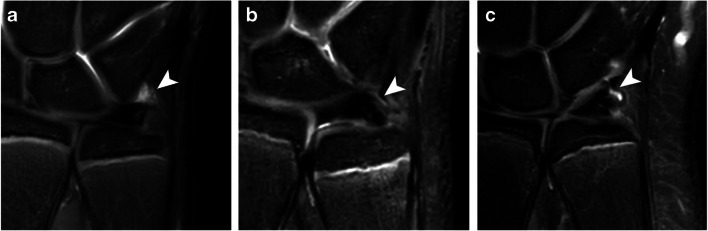

Wrist and ECU tendon position

Neutral wrist position based on the axial plane was seen in 42 (46%) observations. The wrist was defined as supinated in 47 (51%) observations and pronated in 3 (3%). The ECU tendon position was scored as completely positioned within its groove in 51 (55%), as partially within its groove in 31 (34%), and as completely dislocated out of its groove in 10 (11%) observations (Fig. 4). The distribution of ECU tendon positions significantly differed between a supinated and a non-supinated wrist position (p = 0.031, Table 3). Inter-rater agreement for wrist and ECU tendon position was, respectively, substantial (ICC = 0.62, 95% CI = 0.53–0.84) and moderate (ICC = 0.59, 95% CI = 0.46–0.72).

Fig. 4.

Axial T2 weighted fat-saturated MRI showing the ECU tendon (arrowheads) position a completely within, b partially within, and c completely outside its groove (long arrows). All three wrist positions were scored as a supinated wrist position with the ulnar head in dorsal rotation. Image b and c also show a substantial amount of DRUJ effusion (short arrows)